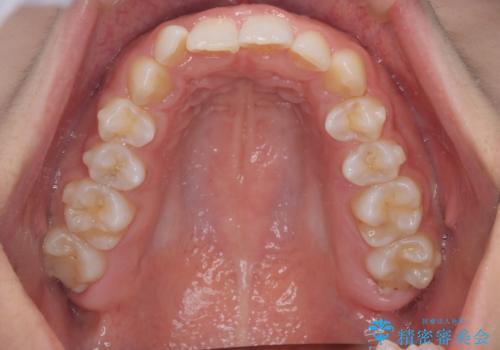

- 患者様は、ディープバイト(深い噛み合わせ)と、咬合平面の左下がりが気になるとのことでご来院されました。診断の結果、非抜歯で治療可能と判断し、透明なマウスピース型矯正装置「インビザライン」を用いる方針としました。治療では、歯列全体の調整を行いながら、咬合平面の水平化を重点的に進める計画を立案しました。2年間で計画的にマウスピースを交換し、左右のバランスと噛み合わせの改善を目指しました。

ディープバイトの矯正は、噛み合わせが深くなりがちなため、細心の注意を払いながら進める必要があります。本症例では、奥歯の高さを調整しつつ前歯の噛み合わせを浅くすることで、全体の咬合バランスを整えました。また、咬合平面の左下がりを修正する過程で、歯列に不均等な力がかからないよう、インビザラインのアタッチメント配置を最適化しました。患者様には装着時間を守っていただき、治療が計画通り進むよう協力をお願いしました。治療終了後には、リテーナーを装着して安定性を確保しました。